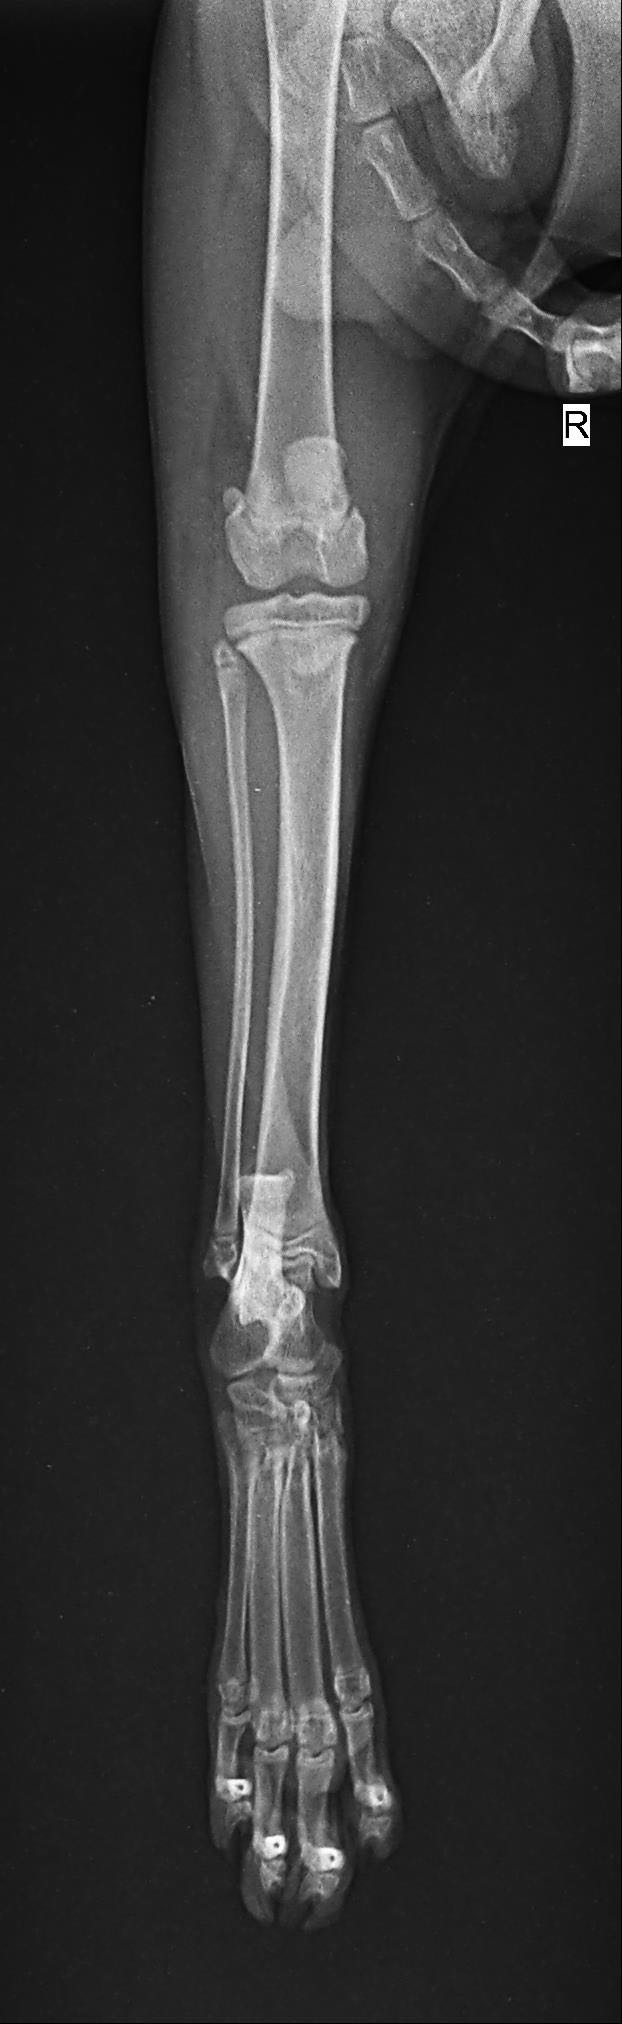

猫瘸了 拍了片

大家帮我看看 去了两家医院 一家建议保守治疗 一家建议动手术治疗